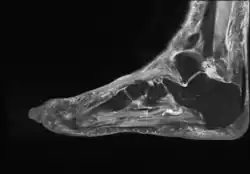

- Achilles bursitis

- Retrocalcaneal bursitis